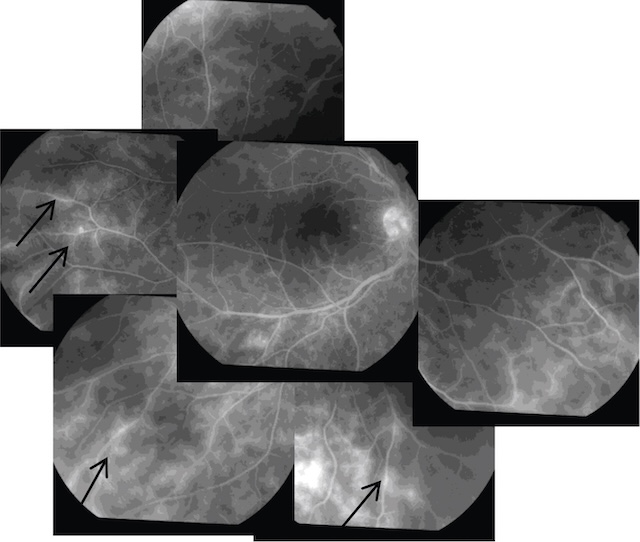

3 Périphlébites rétiniennes

Il s’agit d’engainements blanchâtres des veines rétiniennes périphériques vus au fond d’œil (fig. 19.5).

On note la présence de lésions de vasculites périphériques (périphlébites) (flèches).

Ce montage d’angiographies à la fluorescéine montre plusieurs clichés du fond d’œil, révélant une vascularisation rétinienne périphérique avec de multiples zones de fuite fluorescéinique, visibles sous forme d’hyperfluorescences floues, parfois en nappe, situées surtout au niveau des régions périphériques inférieures et supérieures. Des gaines périvasculaires sont bien marquées, en particulier autour des veines, traduisant une inflammation active. Ces anomalies sont typiques d’une uvéite intermédiaire, souvent rencontrée dans le contexte de pathologies inflammatoires systémiques comme la sclérose en plaques. L'atteinte semble bilatérale et diffuse, sans signes de néovascularisation active.